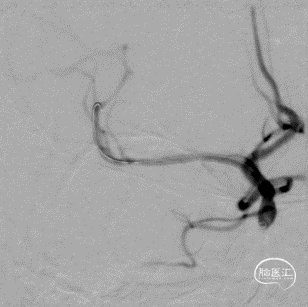

球扩后造影见闭塞段恢复正向血流M1段远端夹层表现。

(2倍速播放)

最后工作位造影和正侧位造影,右侧大脑中动脉区域血流恢复,灌注满意。